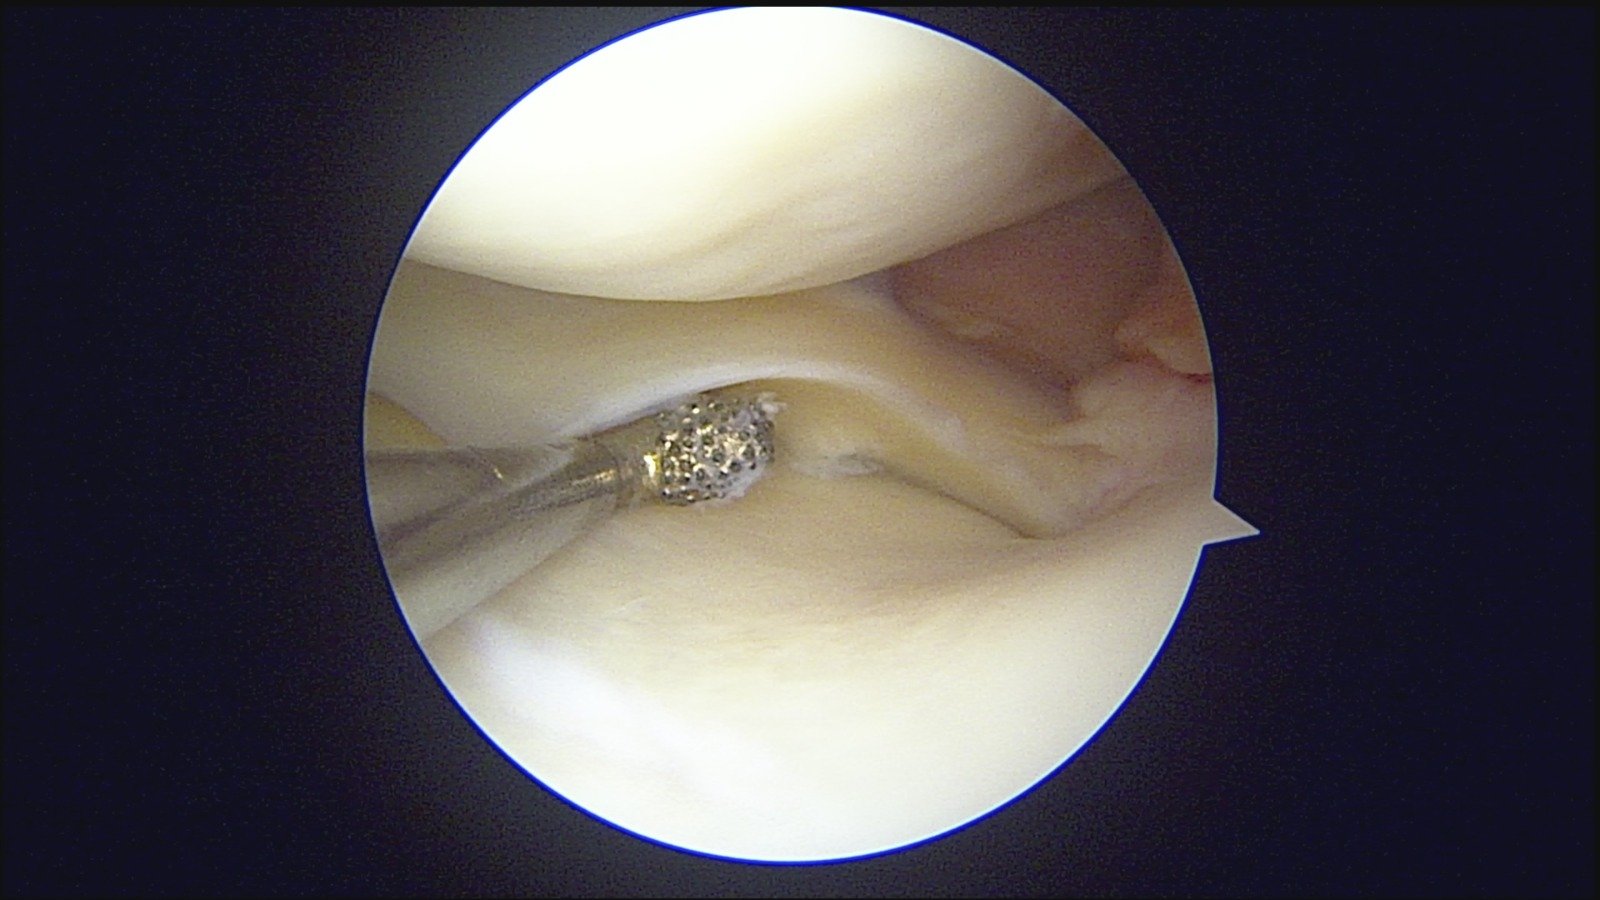

GalleryShoulder rotator cuff repair Meniscus root repair Meniscus repair Bankart repair for recurrent shoulder dislocation ACL reconstruction Machines Instruments